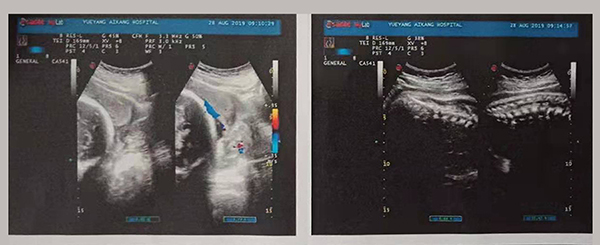

近日,岳陽(yáng)愛(ài)康醫(yī)院產(chǎn)科團(tuán)隊(duì)成功搶救了一名完全性前置胎盤(pán)的產(chǎn)婦。完全性前置胎盤(pán)是妊娠期的嚴(yán)重并發(fā)癥,是分娩期子宮切除的一個(gè)重大高危因素之一,是引起孕產(chǎn)婦死亡和圍生兒死亡的重要原因之一。

2019年8月24日,易女士出現(xiàn)陰道流血,在岳陽(yáng)縣人民醫(yī)院住院,住院期間予以安治、止血,于26日出院。28日早晨6點(diǎn)再次出現(xiàn)陰道流血,量多、顏色鮮紅、三片衛(wèi)生巾均浸透,遂來(lái)岳陽(yáng)愛(ài)康醫(yī)院產(chǎn)科。

易女士一進(jìn)入病房就引起了岳陽(yáng)愛(ài)康醫(yī)院產(chǎn)科主任高君萍的高度重視,考慮到手術(shù)的風(fēng)險(xiǎn)大,手術(shù)過(guò)程復(fù)雜,有可能出現(xiàn)新生兒窒息、產(chǎn)婦大出血等危及母嬰生命的并發(fā)癥,甚至切除子宮可能。在檢驗(yàn)科充分術(shù)前配血、血漿的準(zhǔn)備及全院MDT(多學(xué)科聯(lián)合會(huì)診),立即進(jìn)行手術(shù)。

術(shù)中,擺在產(chǎn)科團(tuán)隊(duì)面前的第一個(gè)嚴(yán)峻考驗(yàn)出現(xiàn)了,整個(gè)子宮下段前壁膨隆血管怒張!迅速設(shè)計(jì)子宮切口,取出胎兒,面臨又一嚴(yán)峻的考驗(yàn),胎盤(pán)大面積植入整個(gè)子宮下段前后壁,迅速行雙側(cè)子宮動(dòng)脈下行支結(jié)扎,迅速人工剝離胎盤(pán)以及卵圓鉗鉗夾剩余胎盤(pán)組織,植入的胎盤(pán)處理干凈后子宮下段前后壁多處肌層缺損伴有大量活動(dòng)性出血,迅速行子宮下段整形修復(fù)縫合止血……不得不說(shuō)產(chǎn)婦是幸運(yùn)的,婦產(chǎn)科、手術(shù)麻醉科等多科通力合作,經(jīng)過(guò)約2小時(shí)的手術(shù)及搶救止血,術(shù)中共計(jì)出血1500ml,輸懸浮紅細(xì)胞4個(gè)單位,終于保得母女平安,并完美的保留了子宮。易女士術(shù)后恢復(fù)良好,對(duì)婦產(chǎn)科的精湛技術(shù)贊不絕口!